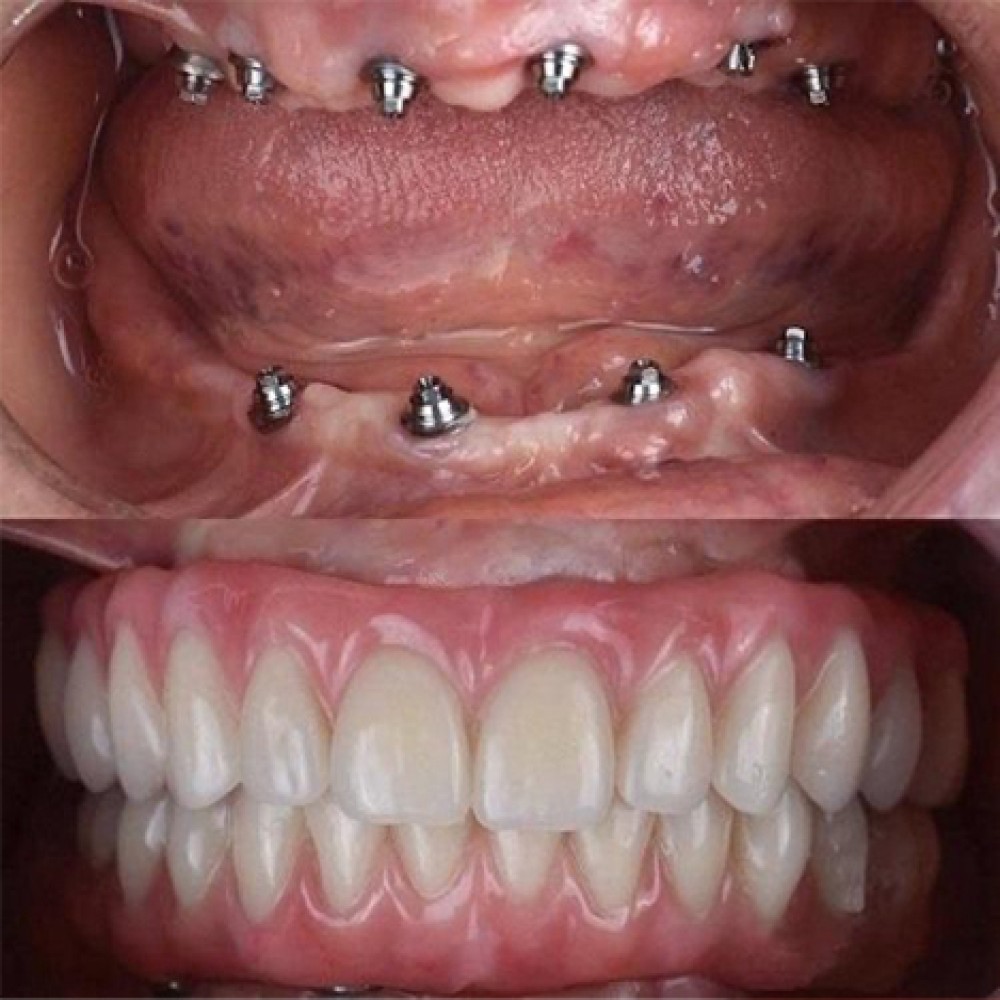

در مرکز تخصصی دکتر محمودی، از بهترین مواد و تکنولوژیهای روز دنیا برای انجام ایمپلنت دندان استفاده میکنیم. شما میتوانید مطمئن باشید که نتیجه کار دائمی و با کیفیت خواهد بود.

ایمپلنت دندان فرآیندی ساده است که با تکنولوژیهای پیشرفته ما، بدون درد و با حداقل زمان به نتیجه میرسد.

با ایمپلنت دندان، نه تنها ظاهر خود را بهبود میبخشید بلکه سلامت دهان و دندان شما هم به شکل قابل توجهی بهتر میشود. ایمپلنتها از تحلیل استخوان جلوگیری میکنند و باعث حفظ ساختار طبیعی فک و دهان میشوند.

مرکز تخصصی دکتر محمودی با بیش از سالها تجربه در ارائه خدمات دندانپزشکی پیشرفته، به شما این اطمینان را میدهد که درمان شما با بهترین کیفیت و در محیطی کاملاً استریل و بهداشتی انجام خواهد شد. پزشکان ما از تکنیکهای نوین و تجهیزات روز دنیا برای انجام ایمپلنت استفاده میکنند.